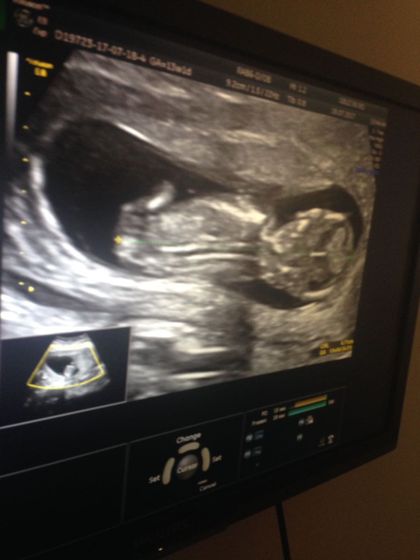

Итак! Все прошло отлично.Вчера очень волновалась, что мужа не пустят на узи)Но Урра! Пустили.С лялечкой все впорядке! Муж расстерялся когда увидел на мониторах настоящего человека с руками, ногами и т.д.Говорит божечки он шевелится????.Стоял и судорожно фотографировал.Лялечка очень активная, сложно было поймать нормальное фото.И все же со спины удалось сфотать.Смотрели двумя датчиками снаружи и внутри.Мочевой пришлось набирать… Срок 13,1 неделя.Ктр 67,1.Чсс 156уд.м, толщина воротникового пространства 1,8.Носовая кость 2,3мм.Кровоток в венозном протоке pi-0,93. По анатомии эмбриона все Б/О.Локализация левая боковая.длинна шейки 40мм.Следом сдала кровь из венки все отлично.Перед узи заставили покушать плотно.На кровь не влияет))Девочки кто разбирается по данным кости носа, не сильно большой?))

Помню свои волнения.Я тоже была в восторге )Это удивительно, вроде такой срок не большой а на мониторе все все все видно.человечище)

Я подумала по фото двойня

Нет это мозг)))))))